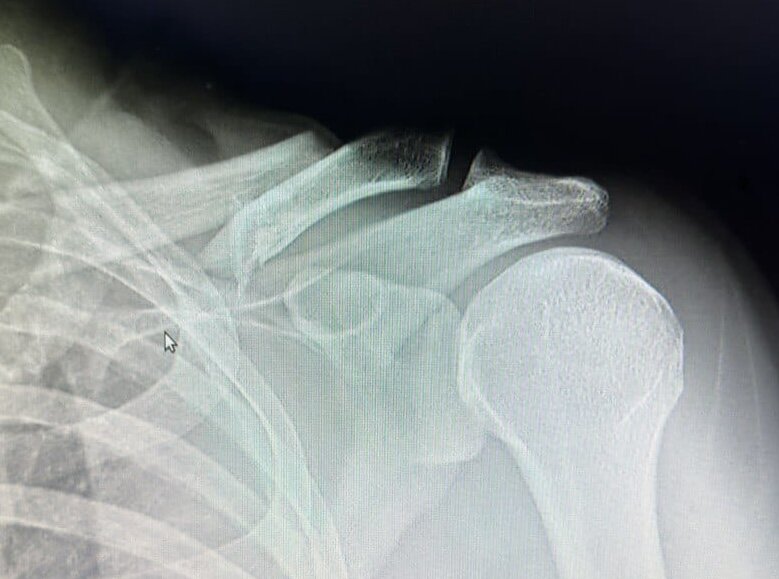

На Бохоле произошло еще одно происшествие с нашим соотечественником, с моим другом, который прилетает сюда на зимовку уже не впервые. Мотоцикл он водит хорошо, одевает шлем. Но в этот раз ехал ночью уставший, резко дал газу на повороте, и упал. Сломана ключица со смещением.

Фото снимка пациента

В госпитале порекомендовали делать операцию, но наши соотечественники отговорили оперироваться на Бохоле, так как есть вероятность некачественной операции. Решается вопрос сейчас о выборе действий из нескольких вариантов: